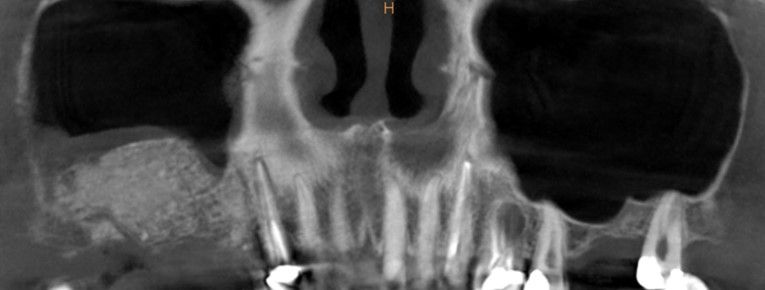

En la exploración radiográfica mediante escáner se apreció una lesión apical de pequeño tamaño en el 1.4 y una escasa disponibilidad ósea. Además, se observó imagen radioopaca cupuliforme de 3 x 2,8 cm en el seno maxilar derecho, compatible con un pseudoquiste sinusal (Figura 2). La extensión craneal alcanzaba la mitad superior del seno maxilar y el volumen de la lesión (5 cm³) era aproximadamente ⅓ del volumen sinusal (Figuras 3 y 4).

Se planificó la exodoncia de los dientes 1.4 y 1.7, cortando la prótesis distal al diente 1.3 y la realización de una elevación de seno maxilar derecha abierta simultánea a la eliminación del pseudoquiste sinusal. Posteriormente su odontólogo habitual rehabilitará el caso con implantes dentales. Se explicó el procedimiento a la paciente y se obtuvo el consentimiento informado para la intervención.